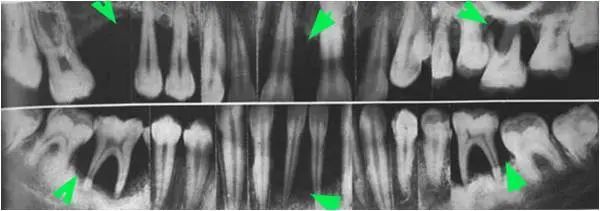

在口腔常规检查中,放射线检查也是很常见的检查方法。而在牙周病检查诊断过程中,最常用的方法是拍全景片,其学名是全口曲面体层片。它的突出优势是可以将整口牙的牙槽骨情况尽收眼底。通过全景片,牙医可以看到牙槽骨是否有吸收,以及发生吸收的牙位、严重程度等,由此辅助诊断牙周炎是否存在和制定牙周治疗计划。牙槽骨吸收的情况也可以反映出牙周炎的严重程度。但这个指标不能凭肉眼判断,只有放射线检查才能帮助我们“看穿”牙槽骨的内部情况。